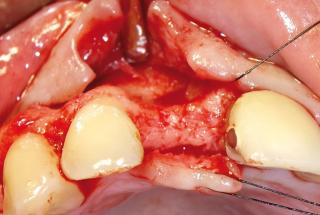

Clinical cases

MPI closely monitors clinical cases in the market to ensure their correct functioning and successful outcome.